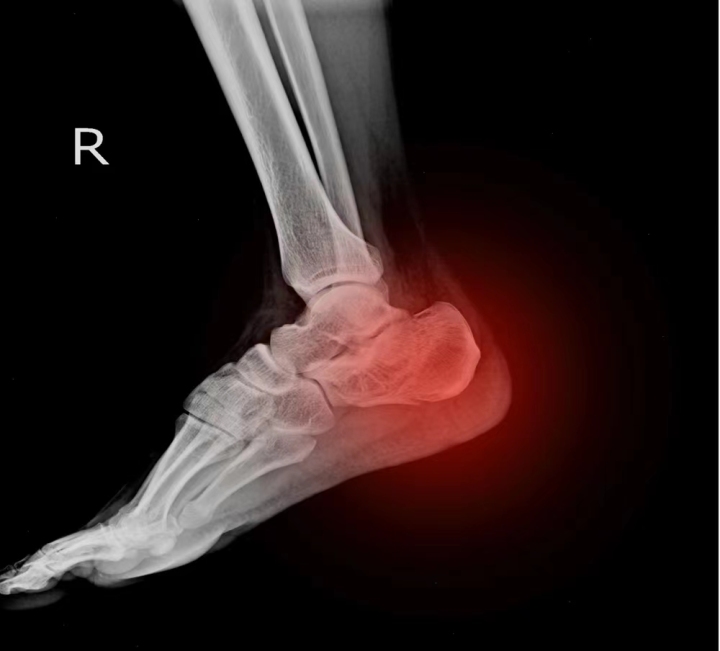

踝關節扭傷可大可小,小的可以是肌腱或韌帶拉傷,大的可以骨折兼軟組織撕裂,後者必須用x光確定。

我對他爸爸說,「軒仔跳高落地的撞擊力相當大,為了排除骨折,我建議先拍個x光……」

「昨天聽你吩咐去了,x光報告沒有骨折,所以趕快來做浮針。」

「骨頭沒事就好。」

這個排除骨折的可能性是需要的,也不用憂慮浮針「再灌注」太大力所造成的負面影響。